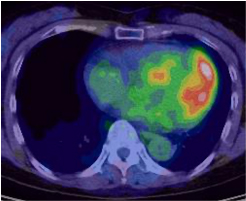

サルコイドーシスは、非乾酪性肉芽腫という病理変化を伴う炎症性疾患です。心臓以外にも眼、皮膚、肺やリンパ節に起こり得ます。心臓においては、心筋の収縮障害から進行すれば心拡大が起きます。不整脈を併発しやすいことも知られています。診断には心臓MRIや血液検査のほかに、心臓にブドウ糖が取り込まれているか調べる核医学検査であるFluorodeoxyglucose-Positron Emission Tomography(FDG-PET)が病勢の把握に有用です。

心サルコイドーシスの活動期

心サルコイドーシスの活動期

ステロイド治療により

ステロイド治療により炎症・免疫反応が軽減